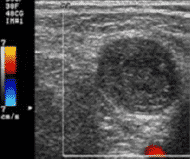

Detección de trombos y hematomas

La detección trombos y hematomas previos y posteriores a la canalización, evita realizar punciones sobre vasos ya dañados y optar por otros más adecuados y normo funcionantes.

En lo que a la técnica se refiere, también se utiliza la sonda lineal de alta frecuencia. En este caso es preferible el uso de Doppler a color, útil también para determinar permeabilidad, aunque también puede emplearse el modo 2D.

En la detección de trombos se puede observar una imagen ecogénica heterogénea que ocupa total o parcialmente la luz venosa y se considera un signo prácticamente patognomónico la imposibilidad de comprimir la luz vascular por completo. Además, si utilizamos Doppler a color aplicado sobre la luz vascular se apreciará ausencia de flujo o algún defecto de repleción.

Los hematomas dan una imagen similar a la del trombo, pero se encontrarán ubicados por fuera del vaso, pudiendo llegar a comprimirlo o desplazarlo.